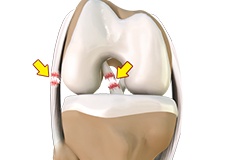

Meniscal Injuries

Meniscal tears are one of the most common injuries to the knee joint. It can occur at any age but are more common in athletes involved in contact sports. The meniscus has no direct blood supply and for that reason, when there is an injury to the meniscus, healing is difficult.